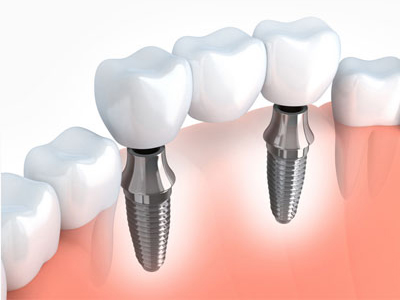

ایمپلنتهای دندانی دائمی چیستند؟

ایمپلنتهای دائمی که به آنها دندان مصنوعی ثابت متکی بر ایمپلنت یا دندان مصنوعی پیچدار نیز گفته میشود، به گونهای طراحی شدهاند که از نظر ظاهری، حسی و عملکردی مانند دندانهای طبیعی شما باشند. این روش شامل قرار دادن پستهای فلزی – معمولاً تیتانیوم یا زیرکونیا – در استخوان فک با جراحی است. با گذشت زمان، این پستها با استخوان جوش میخورند) فرآیندی به نام ادغام استخوانی (و پایداری فوقالعادهای را فراهم میکنند.

دندانهای قابل مشاهده در بالا اغلب از پرسلن یا رزین کامپوزیت ساخته میشوند، به شکل و رنگ سفارشی ساخته میشوند تا کاملاً با لبخند شما ترکیب شوند. برخلاف دندان مصنوعی سنتی، آنها همیشه در جای خود باقی میمانند و نیازی به چسب ندارند.

مزایا

- به شما امکان میدهند با اطمینان کامل غذا بخورید، صحبت کنید و لبخند بزنید.

- با جلوگیری از تحلیل استخوان به حفظ ساختار صورت کمک میکنند.

- بدون لغزش، جابجایی یا تحریک لثه.

- عالی برای بیمارانی که استخوان فک قوی و سالمی دارند.

- ظاهری طبیعی که با سایر دندانهای شما مطابقت دارد.

ایمپلنت ثابت:

- معاینه اولیه و تصویربرداری ) رادیوگرافی یا (CBCT

- کاشت پایه فلزی در استخوان فک

- دوره بهبودی و جوش خوردن پایه به استخوان) ۳تا ۶ماه(

- نصب دندان مصنوعی روی پایه